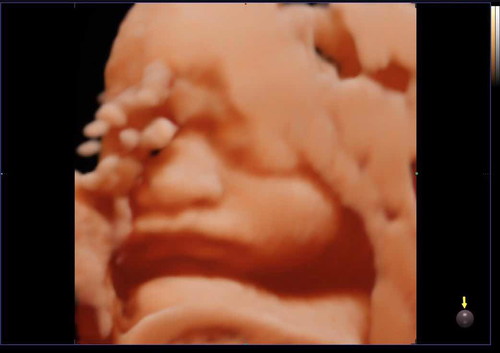

มีน้องๆบ้านไหนตอนซาวด์แล้วชอบเอามือปิดหน้าตลอดไหมคะ ของเรานี่เอามือปิดหน้าทุกครั้งที่ซาวด์ จนคุณหมอบอกรอลุ้นเอาตอนคลอดเลยละกันค่ะ อิแม่ล่ะเพลีย